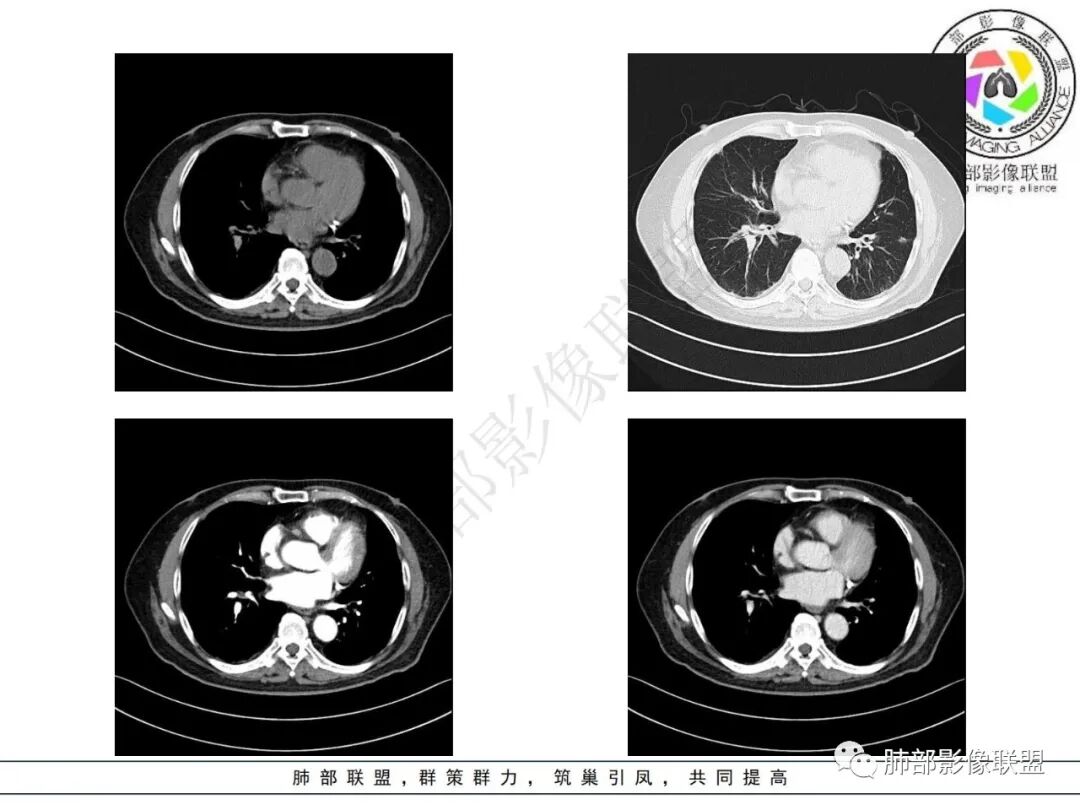

2.影像表现:双肺上叶见结节影及条索影,树丫等,边界可分辨。气管支气管壁广泛增厚、钙化,形态相对均匀一致,上达声门区。支气管膜部受累。增强轻中度强化。纵隔见轻度增大淋巴结。

3.综合分析:双肺上叶病灶较符合继发性肺结核。支气管病变分布具有广泛性、一致性。支气管壁广泛增厚钙化常见于淀粉样变性。累及膜部气管支气管病变的有淀粉样变性和GPA

TBA的临床表现无特异性,常为亚急性,多表现为咳嗽、咳大量白黏痰、胸闷、进行性呼吸困难等。也有报道描述症状为声音嘶哑、痰血,且常被误诊。TBA在胸部CT常表现为管腔不同程度增厚,管壁弥漫性钙化及支气管肿块部分钙化。TBA在支气管镜下可见气管支气管管壁多灶性隆起,或肥厚变形伴管腔不同程度扭曲狭窄,故支气管镜检查对其诊断有重要意义。典型病理学表现为黏膜下淀粉样物质沉积,刚果红染色(+)。